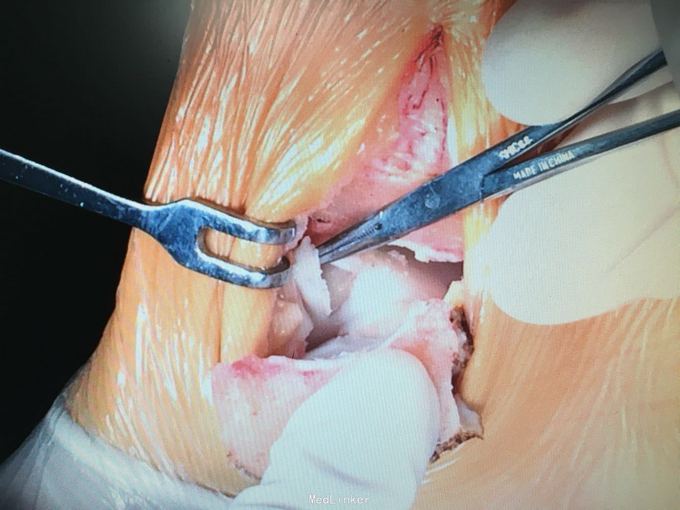

诊断和手术方式如题 直接上图

术后第二天进行非负重下踝泵练习,2周内限制踝关节外翻和外旋,6-8周后根据骨愈合情况下地负重 目前有北京积水潭报道全关节镜下完成此手术,我们将进一步探索,另外,股骨外侧髁非负重区取骨后膝关节痛的情况可见,取骨区域尚需改进